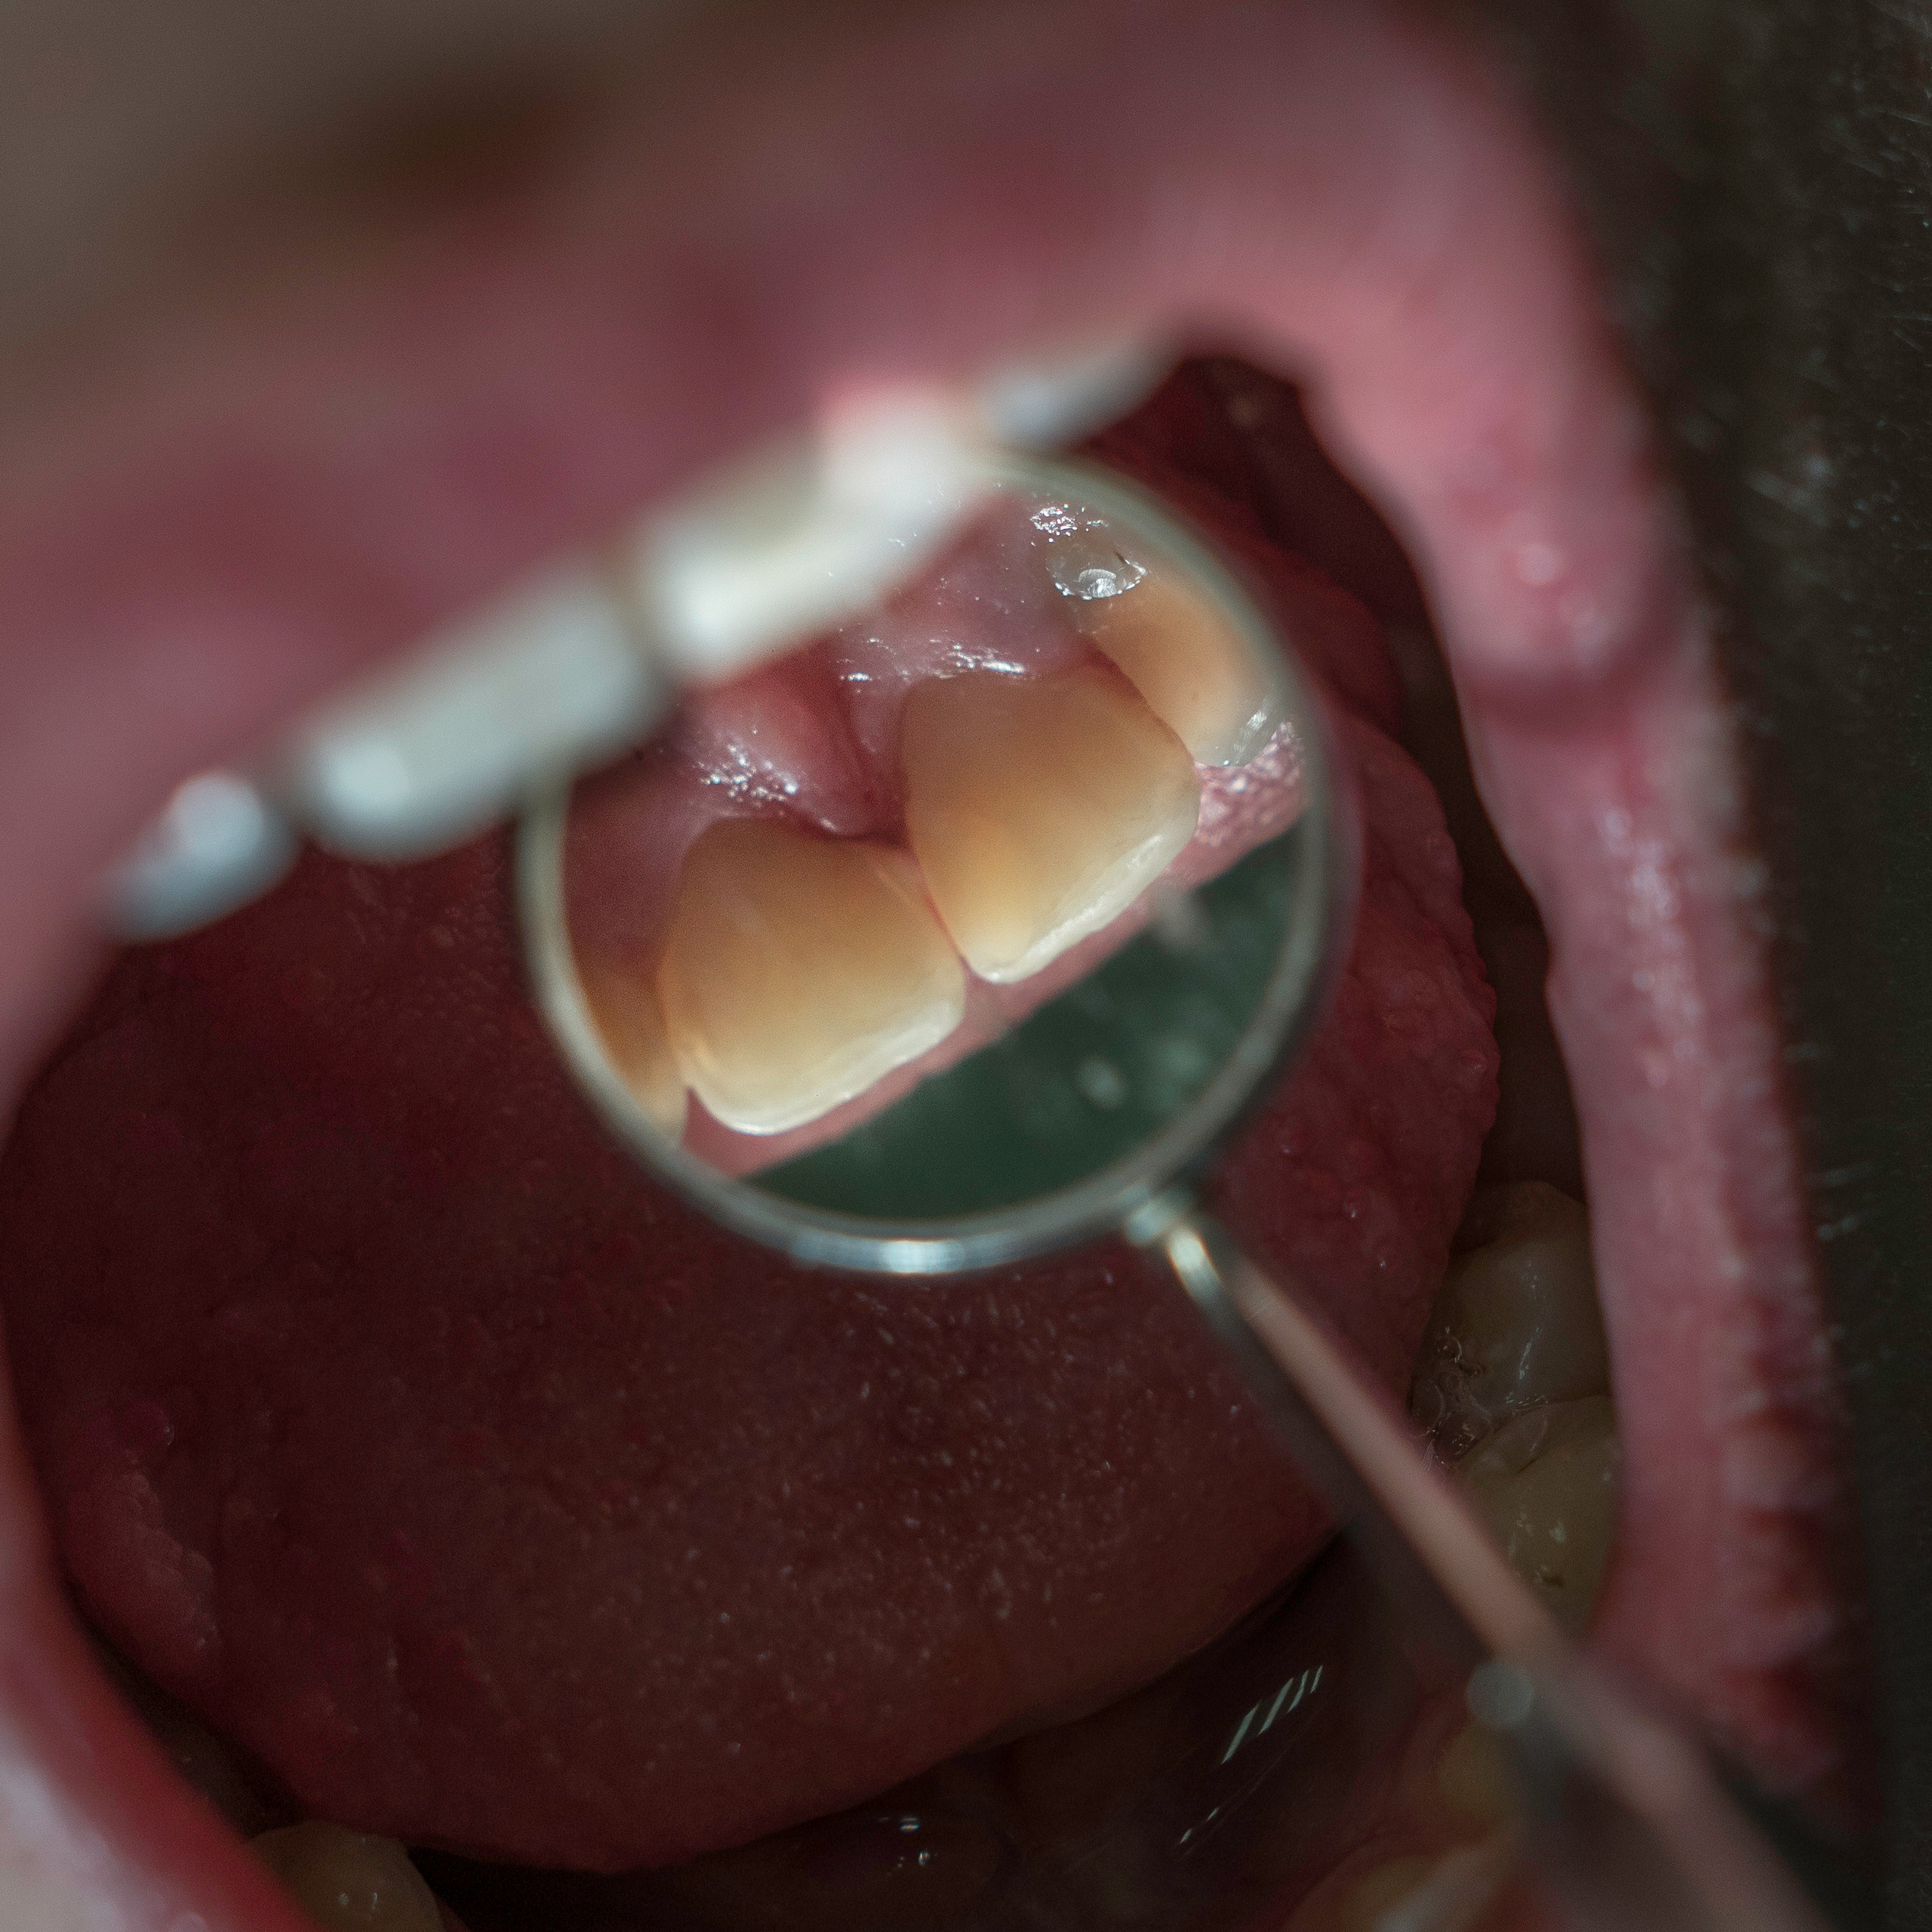

Фотографии учеников до обучения

Фотографии после обучения